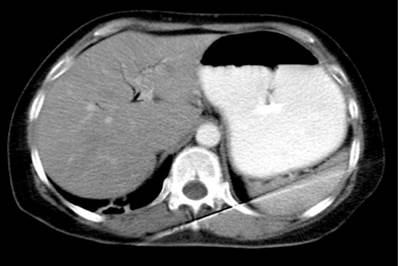

En TACab se evidencia obstrucción intestinal por imagen intraluminal a nivel de la primera porción duodenal de 4,5 x 3 cm (Figura 1 y 2) asociado con neumobilia y presencia de paso del medio de contraste a la vía biliar, lo que cumple los criterios de la triada de Rigler, adicionalmente dilatación de la cámara gástrica secundaria a obstrucción de la luz duodenal y una EVDA con presencia de cálculo impactado en el bulbo duodenal (Figura 3 y 4).

Figura 1 Tomografía axial computarizada de abdomen que evidencia la presencia de imagen redondeada que obstruye la luz duodenal.